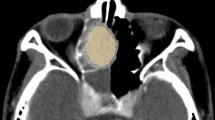

Olfactory neuroblastoma (ONB), also known as esthesioneuroblastoma (ENB), is a rare malignant neoplasm of the sinonasal cavity first described in 19241. It has an incidence of 0.4 cases per million and accounts for ~6% of all sinonasal malignancies2,3. ONB is thought to arise in the olfactory epithelium at the anterior skull base and superior aspect of the sinonasal cavity4. These locally aggressive neoplasms invade the nasal cavity, paranasal sinuses, cribriform plate, intracranial space, and orbit and can metastasize to the neck, central nervous system, and bone4,5. In cases amenable to surgery, resection followed by postoperative radiotherapy is the most commonly used treatment; for patients with unresectable or metastatic disease, chemotherapy and radiation are used4. Despite multi-modality therapy, the 10-year overall survival rate for patients with ONB is ~50%4,6. Therefore, there is a great need for a better understanding of the pathogenesis of this tumor type, which could inform improved diagnostic and therapeutic strategies.

To investigate global genomic losses or gains that are common in ONB, we next used a SNP array approach. Initially, SNP array studies with an Illumina Beadchip containing 300,000 markers were performed on 10 ONB tumor samples and multiple abnormalities were observed. Most abnormalities involved copy number changes (loss or gain) of entire copies of chromosomes. Given the extent of copy number alterations, it was not possible to precisely determine tumor cell ploidy status based on the SNP array. Therefore, we focused our analysis on structural changes, such as deletions and duplications, within chromosomes. Similar to the WGS data, we observed recurrent deletions in chromosome Xp21.1. Deletions were observed in 9 of the 10 tumors (Table 1). In seven of the eight tumors from male patients, these deletions involved the DMD coding region and in five of these seven tumors, the deletion extended into the 5′ UTR. In the tumor from an additional male patient (ENB7PT2), the deletion was 102 kb upstream to the DMD gene but encompassed three CTCF-binding motifs that could affect transcriptional activity. One tumor from a female patient (ENB09PT1) showed loss of one allele of chromosome X (Fig. 1a). Only one of the 10 tumors (from the other female patient, ENB03PT2) did not show any detectable structural abnormality in the X chromosomes. Interestingly, this patient did have a homozygous deletion in LAMA2, the gene encoding the alpha 2 chain of laminin (Supplementary Figure 2).